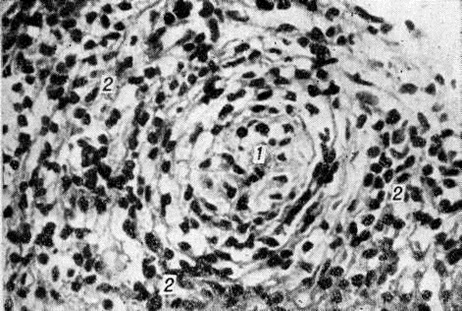

Рис. 1.

Микроскопическая картина лепроматозной гранулемы в коже: отчётливо видна свободная от инфильтрации субэпидермальная зона. Окраска гематоксилин-эозином; × 80. 1 — •эпидермис, 2 — субэпидермальная зона, 3 — инфильтрат.

Рис. 1—6.

Микроскопические картины поражений при различных формах лепры.